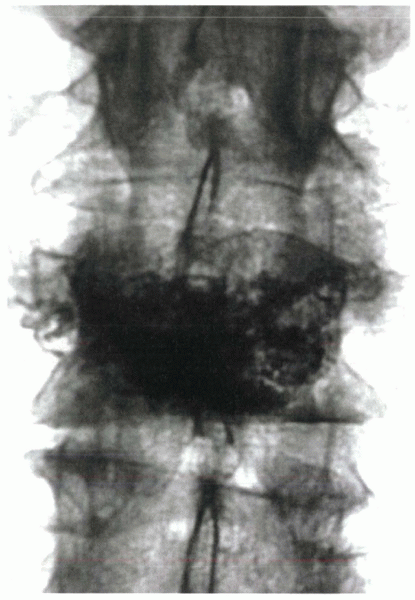

![]() |

Figure 24-4

An 84-year-old man complained of severe sacral pain after “sitting down too hard.” He was point tender over the sacral body, and his pain increased with Patrick’s test. Initial antero-posterior (A) and lateral (B) radiographs show only osteopenia. Scintigraphy in patients with sacral insufficiency fractures generally shows intense uptake, often in an “H” pattern, over the sacrum (C). This patient was mobilized gradually, but sustained a second episode of falling into his hard kitchen chair. New lateral radiographs showed complete displacement of the S1-2 segment. CT scan with sagittal reconstructions shows a transverse fracture through S1-2 (D). MRI typically shows an abnormal signal pattern through the sacral ala (E). After his second fall, the patient reported urinary retention and ultimately was admitted to the hospital for pyelonephritis. He had toe flexor weakness. He underwent a laminectomy and noted improvement in neurologic symptoms (F). |

Figure 24-4 (Continued)